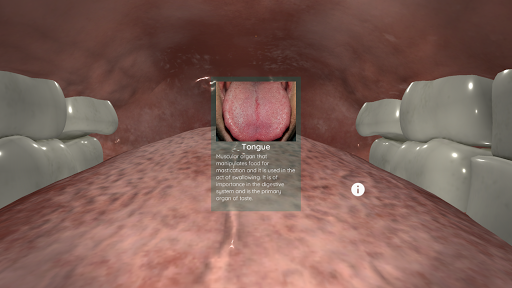

Anatomyou VR to edukacyjna aplikacja mobilna, która prezentuje w sposób wciągający ludzką anatomię.

Korzystając z wirtualnej rzeczywistości, będziesz w stanie poruszać się wzdłuż struktur anatomicznych, stając się częścią ludzkiej anatomii: układu rozrodczego układu krążenia, oddechowego, trawiennego, moczowego, łzowego i żeńskiego.

Anatomyou VR może być używany w dwóch różnych trybach: Virtual Reality i Fullscreen.

Mimo że zapewnia najlepszą jakość w trybie Virtual Reality, użytkownik może również korzystać z tej aplikacji mobilnej w trybie pełnoekranowym, bez potrzeby korzystania z gadżetu rzeczywistości wirtualnej.